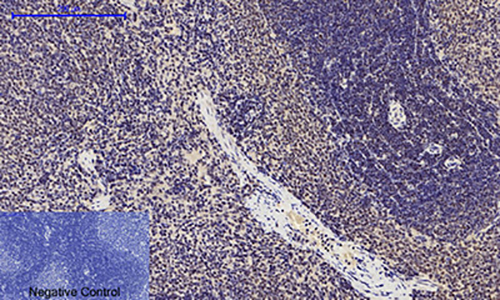

WB,IHC-F,IHC-P,ICC/IF,IP,ELISA

WB: 1:500-1:1000 IHC: 1:50-1:100 IF: 1:50-1:200 IP: 1:20 ELISA: 1:10000